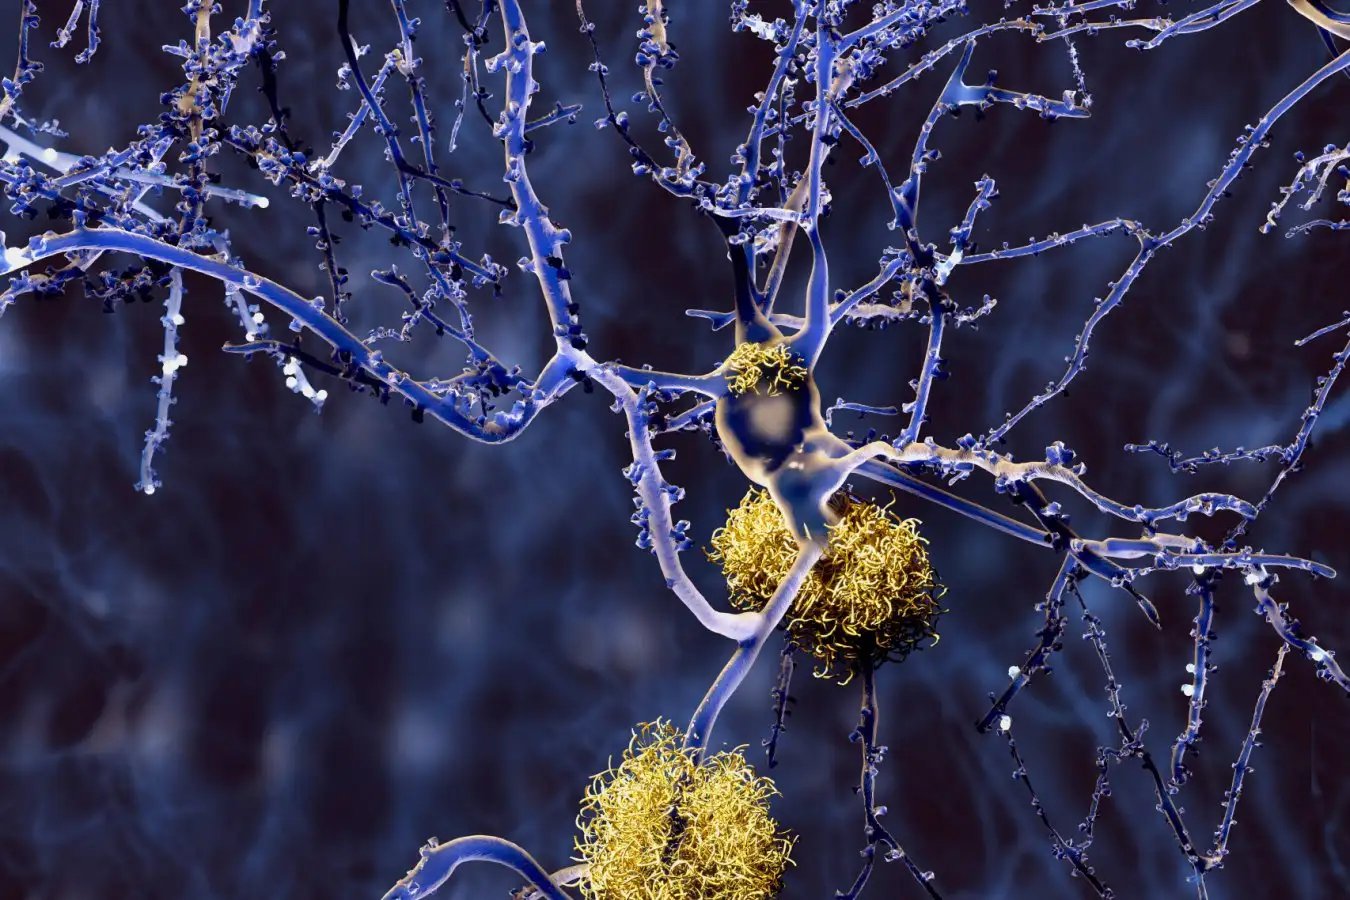

The bioink consists of two compounds commonly used for 3-D printing implants: hydroxyapatite, which supports bone formation pathways and enhances tissue regeneration, and a biocompatible plastic called polycaprolactone, or PCL, which becomes the scaffold for bone growth.

“PCL is [approved by the U.S. Food and Drug Administration] and gradually degrades in our body over months,” Lee says. “This enables the slow substitution of the graft with the newly grown bone tissue.” The proportions of the two compounds can be adjusted to optimize the material’s strength, stiffness and biochemical properties for each use. The researchers also incorporated antibiotics into the bioink to prevent postoperative infections.

Lee and his colleagues tested the glue gun and bioink on femoral bone fractures in rabbits. Comparing results from rabbits receiving the therapy with a control group receiving regular bone cement, the team found that the former group had better healing and regeneration of bone tissue. The animals also showed no signs of infection during the 12 weeks following surgery.